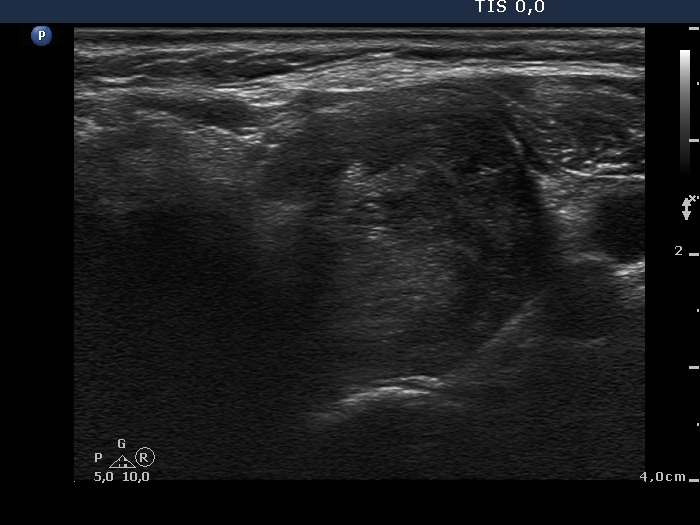

Follow-up investigation 6 months after first visit (third row of images):

Clinical presentation. The patient refused our suggestion and went on conservative therapy. She had no complaints.

Palpation: unchanged.

Results of blood tests: euthyroidism on daily 5 mg methimazole (TSH 1.17 mIU/L, FT4 17.2 pM/L).

Ultrasonography. Except for a minimal decrease in hypoechogenicity and in the vascularization the pattern was unchanged.

TSAb was already elevated 8.7 U/mL (normal value below 1.5).